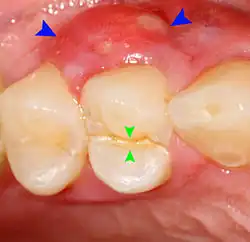

Pericoronitis is inflammation of the soft tissues surrounding the crown of a partially erupted tooth.[25] The lower wisdom tooth is the last tooth to erupt into the mouth, and is, therefore, more frequently impacted, or stuck, against the other teeth. This leaves the tooth partially erupted into the mouth, and there frequently is a flap of gum (an operculum), overlying the tooth. Bacteria and food debris accumulate beneath the operculum, which is an area that is difficult to keep clean because it is hidden and far back in the mouth. The opposing upper wisdom tooth also tends to have sharp cusps and over-erupt because it has no opposing tooth to bite into, and instead traumatizes the operculum further. Periodontitis and dental caries may develop on either the third or second molars, and chronic inflammation develops in the soft tissues. Chronic pericoronitis may not cause any pain, but an acute pericoronitis episode is often associated with pericoronal abscess formation. Typical signs and symptoms of a pericoronal abscess include severe, throbbing pain, which may radiate to adjacent areas in the head and neck,[21][26]: 122 redness, swelling and tenderness of the gum over the tooth.[27]: 220–222 There may be trismus (difficulty opening the mouth),[27]: 220–222 facial swelling, and rubor (flushing) of the cheek that overlies the angle of the jaw.[21][26]: 122 Persons typically develop pericoronitis in their late teens and early 20s,[28]: 6 as this is the age that the wisdom teeth are erupting. Treatment for acute conditions includes cleaning the area under the operculum with an antiseptic solution, painkillers, and antibiotics if indicated. After the acute episode has been controlled, the definitive treatment is usually by tooth extraction or, less commonly, the soft tissue is removed (operculectomy). If the tooth is kept, good oral hygiene is required to keep the area free of debris to prevent recurrence of the infection.[21]: 440–441

Sometimes the symptoms reported in the history are misleading and point the examiner to the wrong area of the mouth. For instance, sometimes people may mistake pain from pulpitis in a lower tooth as pain in the upper teeth, and vice versa. In other instances, the apparent examination findings may be misleading and lead to the wrong diagnosis and wrong treatment. Pus from a pericoronal abscess associated with a lower third molar may drain along the submucosal plane and discharge as a parulis over the roots of the teeth towards the front of the mouth (a "migratory abscess"). Another example is decay of the tooth root which is hidden from view below the gumline, giving the casual appearance of a sound tooth if careful periodontal examination is not carried out.